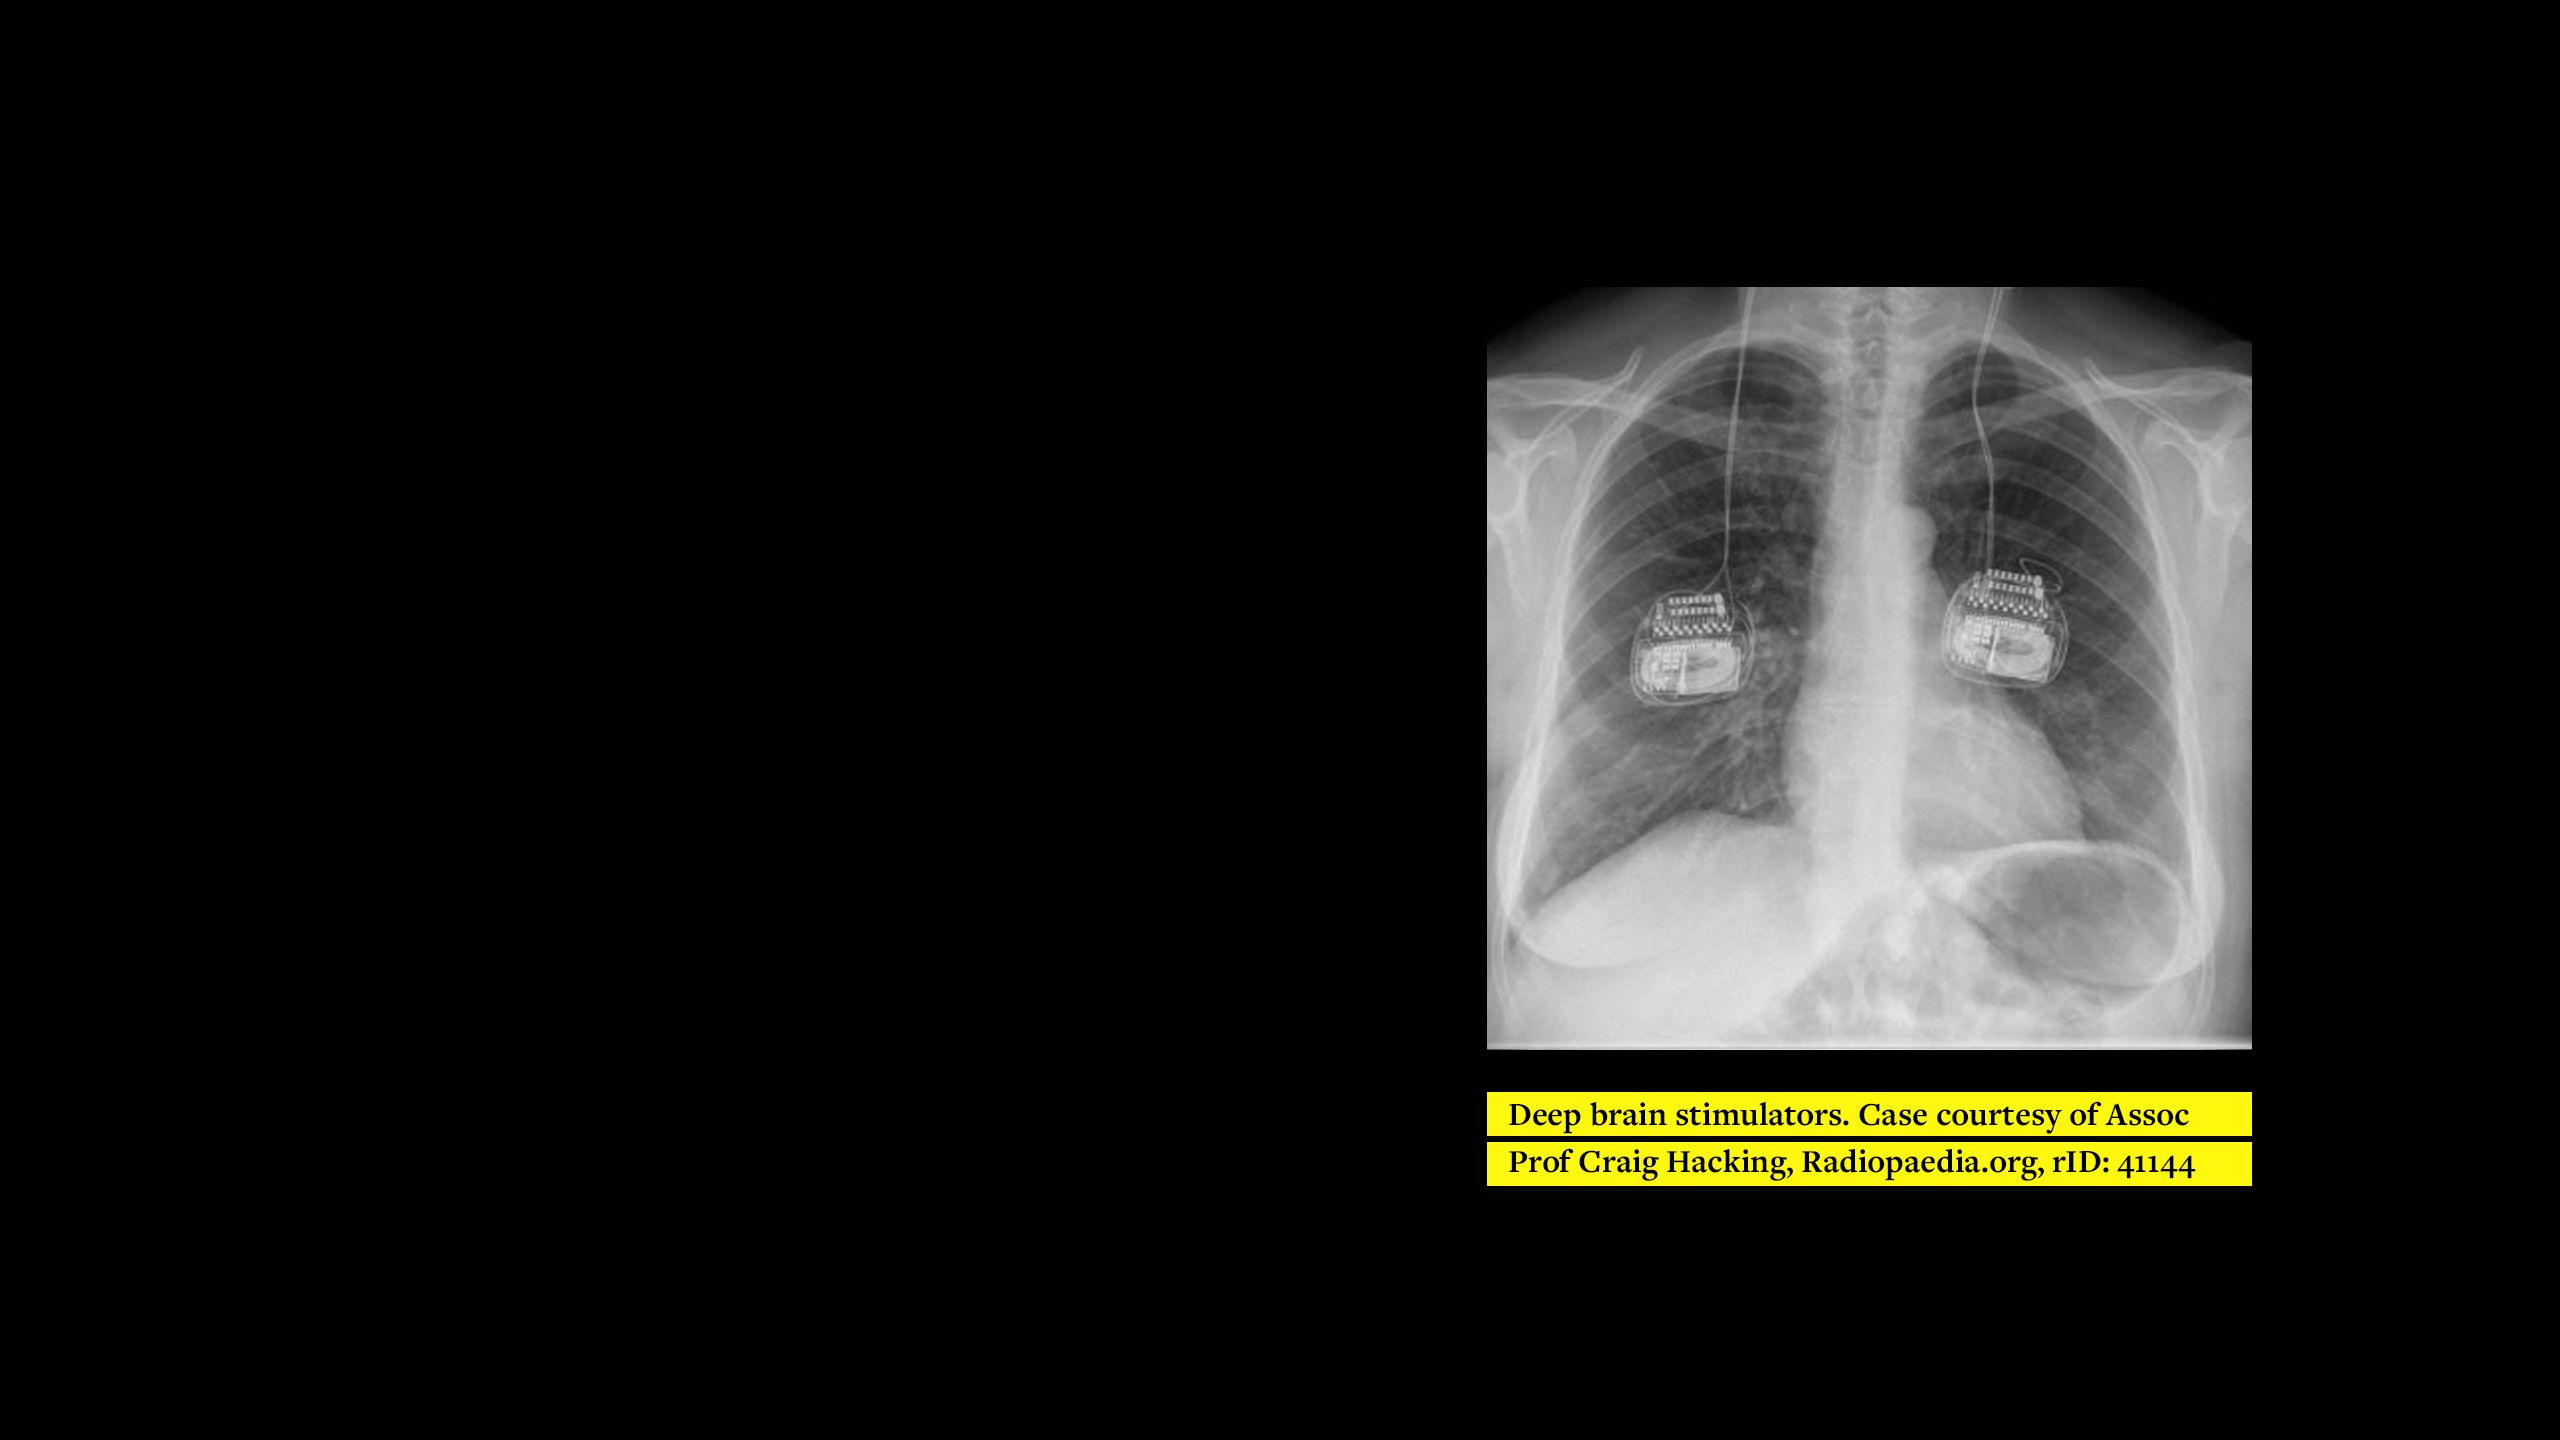

This e-learning programme is designed to raise awareness of different medical devices and to allow better utilisation of X-rays to confidently find and name them. While open to everyone, the training is specifically designed for Diagnostic and Therapeutic Radiographers for MRI safety screening. It is meant to highlight implants that may be specific to certain specialities; for example, cardiac or neuro, and therefore difficult to identify in departments outside of those specialities. Additionally, implants may be commonly known, but not easily recognisable on imaging. It also hopes to appeal to radiographers with different levels of experience and knowledge.

The training describes the appearance and most common locations of each implant and tries to explain various ways of differentiating between implants where possible. The reason for implantation is also stated to further assist identification and allow correlations to be made with the patient’s given information and medical records.

The ‘chest’ module represents the first of four to focus on implanted medical devices. The next modules in the series (abdomen/pelvis, head/neck and extremities) are under development and are due to be released soon.